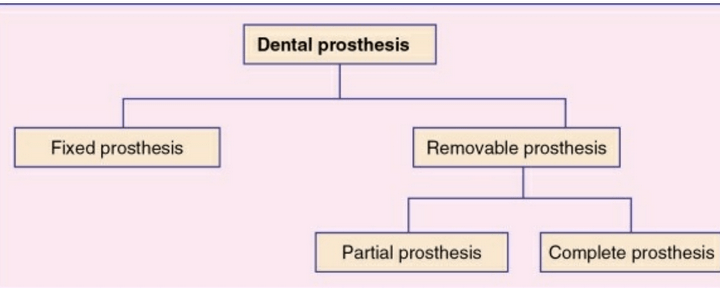

Prosthesis may be defined as an artificial replacement of a missing part of the human body

i. Dental prosthesis

ii. Maxillofacial prosthesis

iii. Ancillary prosthesis

An artificial replacement of one or more teeth and associated dental/alveolar structures.

Any dental prosthesis that is cemented, screwed or attached to the retained natural teeth or roots.

Any dental prosthesis that replaces some of the missing teeth in a partially edentulous arch

The prosthesis that replaces some of the teeth in a partially edentulous arch and that can be removed from the mouth by the patient.

It can be a simple removable partial denture fabricated in acrylic resin called temporary partial

denture.

A removable partial denture fabricated in cast metal alloy and acrylic resin is called cast partial denture

The prosthesis that replaces the entire dentition and associated structures of maxilla and mandible

The prosthesis that is used to replace a part or all of any stomatognathic or craniofacial structures.

Examples of the maxillofacial prosthesis are auricular

prosthesis, orbital prosthesis, nasal prosthesis and facial prosthesis.

The prosthesis that is used to replace the missing teeth , retained by implant supported prosthesis.

The type of dental prosthesis used in prosthodontics for a very short term of usage

example- splints ,stents and guides